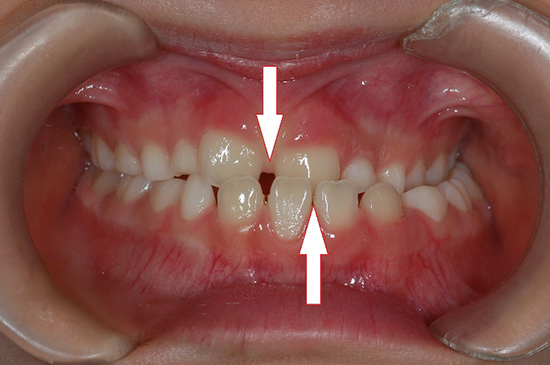

マウスピース型矯正装置

(インビザラインファースト・薬機法対象外)

(マイオブレース)

(マイオブレース)